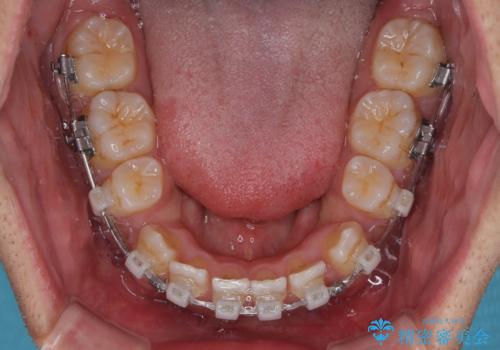

八重歯と前歯のガタガタを抜歯矯正で治療|クリアブラケット使用例

- 矯正装置

- クリアブラケット

- 「八重歯を治したい」とご相談いただいた患者様の症例をご紹介します。

上下の前歯部に強い叢生(ガタガタの歯並び)があり、そのまま歯を並べると出っ歯になってしまう可能性がありました。

そこで、上下左右の第一小臼歯を抜歯し、歯が並ぶためのスペースを確保し叢生を解消する治療計画を立てました。

矯正装置は、審美性と費用面のバランスを考慮して、プラスチックブラケットとメタルワイヤーを使用しました。

透明感のあるブラケットを用いたため、従来の金属装置よりも目立ちにくく、日常生活での見た目の不安も軽減できます。